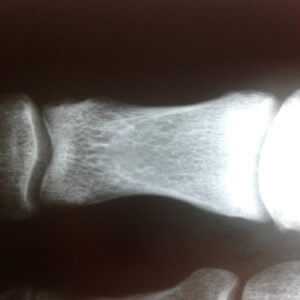

- кисты - новообразования округлой формы, расположенные в центральном или субхондральном отделах костного эпифиза;

Рентген кистей рук при ревматоидном артрите - важная диагностическая процедура, которая позволяет точно выявить стадию развития заболевания. Главными рентген-признаками данной патологии являются припухлости мягких тканей сустава. Также об артрите свидетельствует незначительное сужение межсуставной щели и визуализируемый остеопороз. На более поздних стадиях развития патологии будут видны эрозии костей, которые имеют вид некрупных краевых дефектов в суставных концах костей. В эпифизах костей фаланг пальцев могут виднеться округлые просветления.

При проведении рентгена кистей рук с функцией увеличения изображения можно выявить нарушение целостности замыкающих пластинок уже на первых стадиях развития ревматоидного артрита. По мере прогрессирования заболевания будет наблюдаться ухудшение картины - сустав будет становиться всё уже, появятся очаги эрозии, станет ярче выраженность остеопороза. В результате разрушения суставных концов кости могут появиться подвывихи.